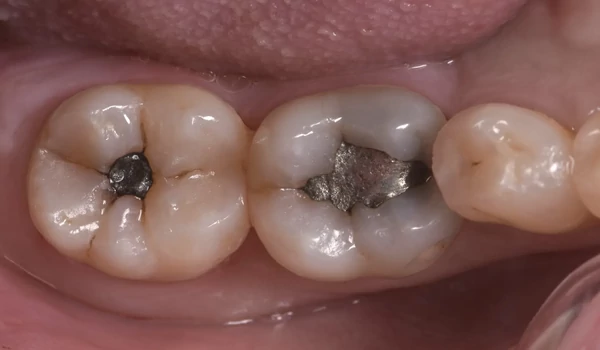

Okkluzális morfológia 7. ábra: occlusalis felszín formázása A LOW változat mérsékelt folyékonysága lehetővé tette az okkluzális barázdák és csücskök alapformázását.

Polírozás 8. ábra: végleges restauráció magasfényű polírozással A restaurációk néhány másodperc alatt magasfényűre polírozhatók voltak, ami esztétikus, sima felszínt és hosszú távon jobb plakkrezisztenciát biztosít.

7. ábra Szép felületi morfológia és árnyalatbeli beolvadás. |

8. ábra A kezelés eredménye a kofferdam eltávolítása után. A restaurációk szépen illeszkednek a környező fogazathoz – színárnyalat és felületi fényesség. |